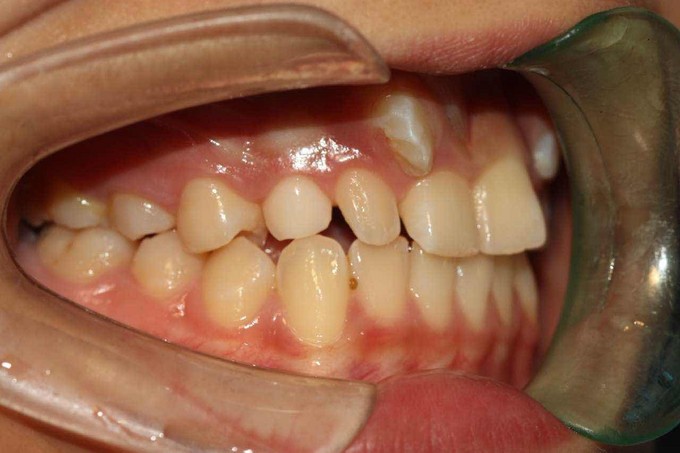

尖牙错位,2过小牙

患者:女,19岁,主诉牙齿不齐,希望矫治。 检查:13根在11和12之间,23根在22唇侧,12和22为过小牙